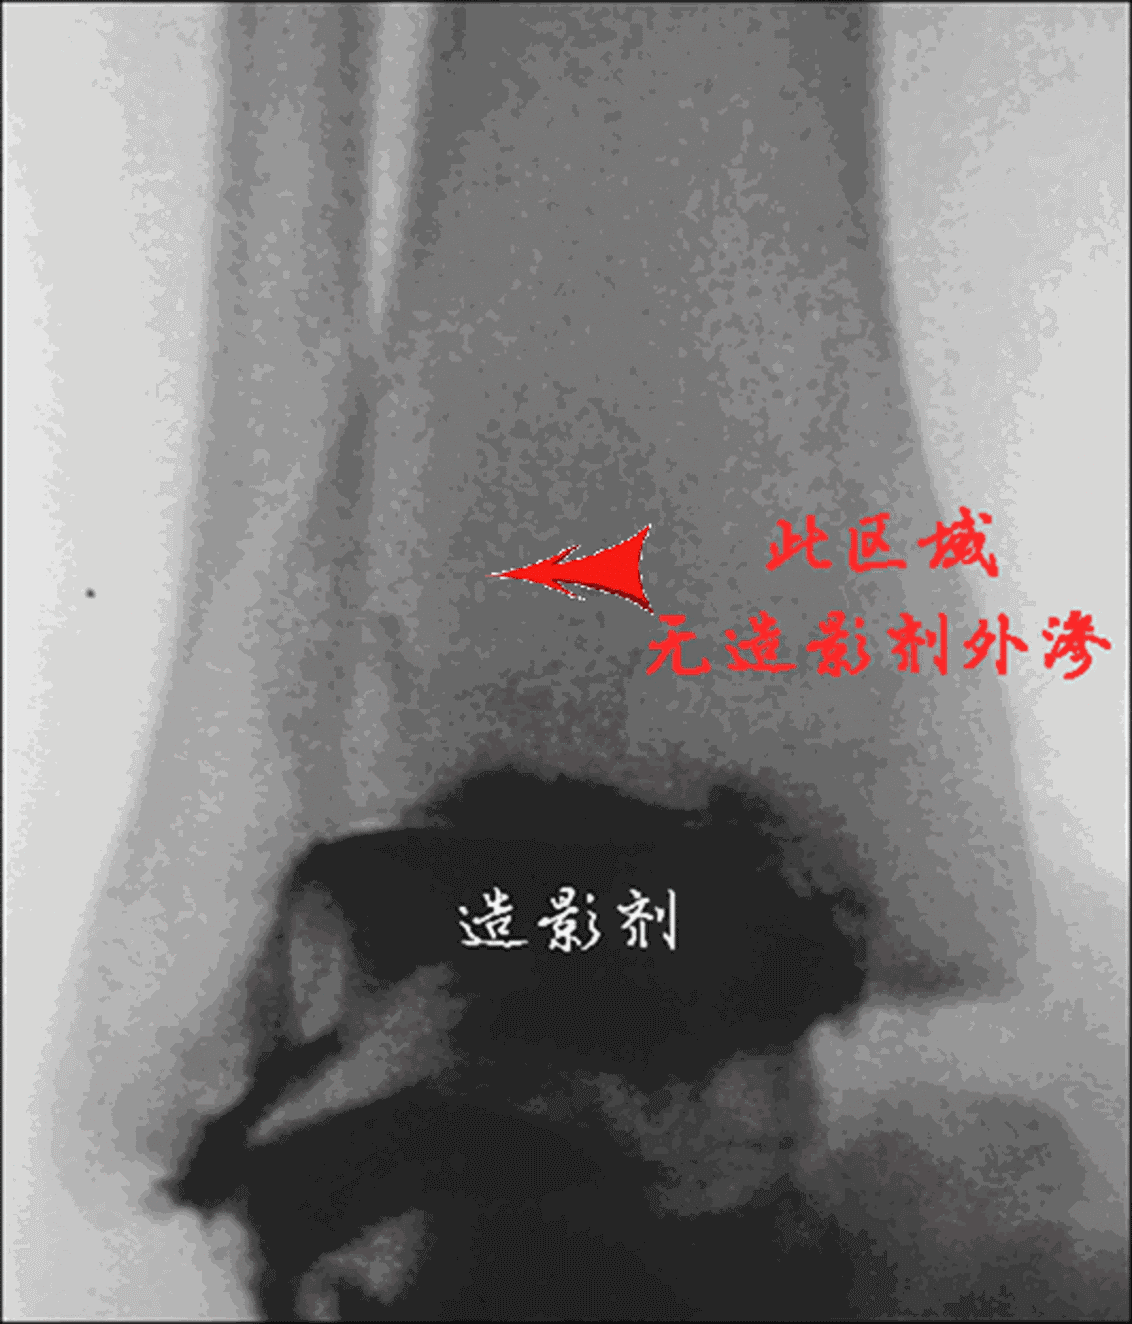

注射针头国际标准

常规手术固定骨折,继而用细穿刺针(22G 腰穿针-相当于6.5号针头,内径0.41mm)在透视下插入踝关节前外侧关节腔,透视踝穴位下注入 2~4 mL 的造影剂(可以1:1盐水稀释)。若造影剂流向下胫腓联合区域,出现「泛溢」现象,说明造影剂渗至损伤的下胫腓联合。若无下胫腓联合损伤,造影剂则局限于踝关节区域,此即 Chertsey 试验阴性。

下胫腓无分离-关节腔内注入造影剂

下胫腓无造影剂泛溢

Chertsey 试验阴性

下胫腓分离-关节腔内注入造影剂

下胫腓出现造影剂泛溢

Chertsey 试验阳性

下胫腓固定准确-关节腔内注入造影剂

造影剂有时可少量渗入至下胫腓联合,但仍可看到一个清晰的踝关节边缘,而非 Chertsey 试验阳性时的「泛溢」表现。 Chertsey 试验可重复检查腓骨是否解剖复位,造影剂一般可在 10~15 min 内吸收。

有时, Chertsey 试验可发现三角韧带嵌入现象,可内侧切开处理韧带嵌顿,继而行腓骨固定。

Chertsey 试验见三角韧带嵌顿

作者强调:Chertsey 试验只能用于判断下胫腓联合是否存在损伤。与拉钩试验相同,Chertsey 试验并不能预测损伤程度,只有骨间韧带完全断裂才表现 Chertsey 试验阳性,所以在下胫腓联合轻度损伤时可表现为阴性结果,此试验最大意义-术中检验下胫腓固定是否准确。

友情提示:造影剂应做过敏试验!